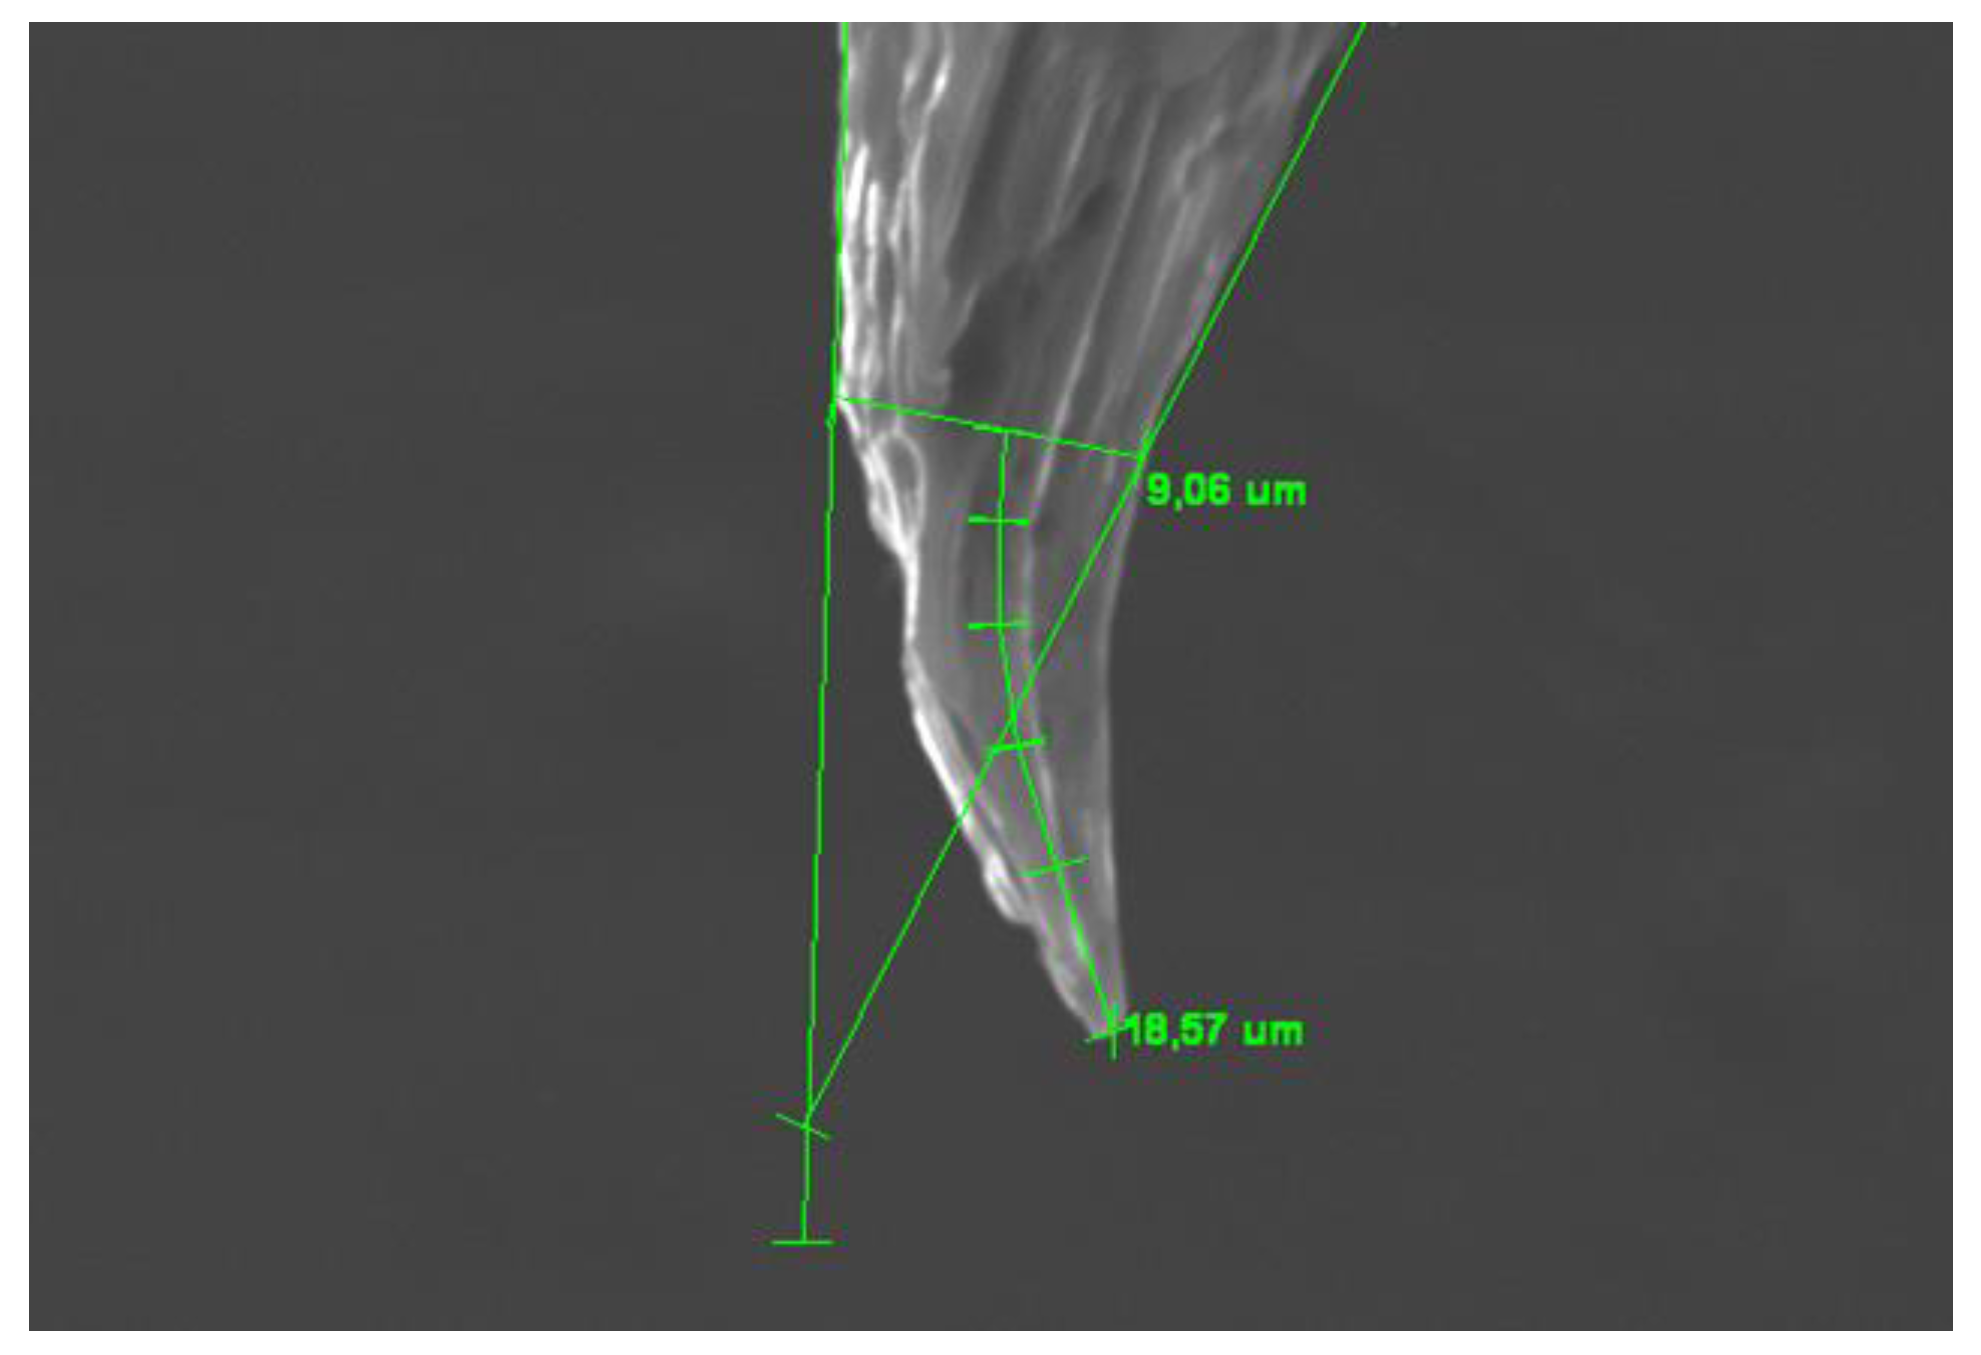

In order to quantify the deformations, two different measurements were carried out on the scanning electron microscopy images. The first measurement refers to the length of the deformed portion of the needle (Figure 6 and Figure 7).

The second measurement was carried out to evaluate how much the deformations protruded on the needle profile with the aim of relating this parameter to the danger of the hook created on the bevel (Figure 8).

Figure 7. Example of strain measurement. (Deformation length=18.57 µ, bevel thickness at the beginning of deformation=9.06 µ,).